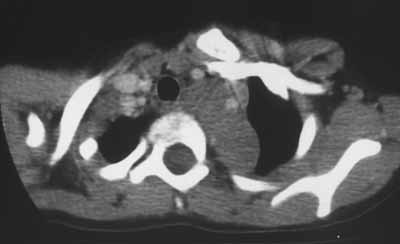

Рис. 2. Ганглионеврома верхнего средостения у больной С., 10 лет. КТА артерий дуги аорты. Левая подключичная артерия расположена в толще опухоли, левая общая сонная артерия оттеснена кпереди.